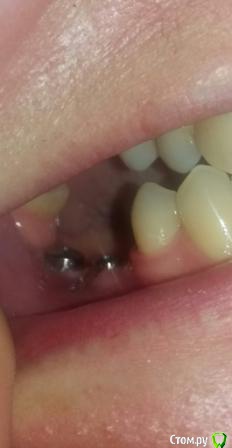

Oksana-p Опубликовано 23 мая, 2016 Автор Поделиться Опубликовано 23 мая, 2016 Ну 8й не проблема. Что касается остального, то нужны новые снимки и желательно внутриротовые фото Если подойдет -то вот фото на телефон (извиняюсь за качество, вечером попрошу кого-нибудь сфотографировать) Ссылка на комментарий

Oksana-p Опубликовано 24 мая, 2016 Автор Поделиться Опубликовано 24 мая, 2016 Еще сфоткала. На снимок ехать 200 км. Мне хирург почему-то его после установки формирователей даже не сделал. Как назло, и десна возле последнего импланта слева болит при надавливании и ноет. Полощу хлоргексидином. Позвонил хирург, сказал, что у меня все "в норме", что у меня уже лучше ничего не получится, что слишком тонкая кость, типа - скажите спасибо "хоть так поставили". Ссылка на комментарий

Oksana-p Опубликовано 15 июня, 2016 Автор Поделиться Опубликовано 15 июня, 2016 Вот такая ситуация сейчас..... Ссылка на комментарий